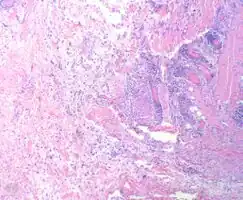

- Myxofibrosarcoma-pathology